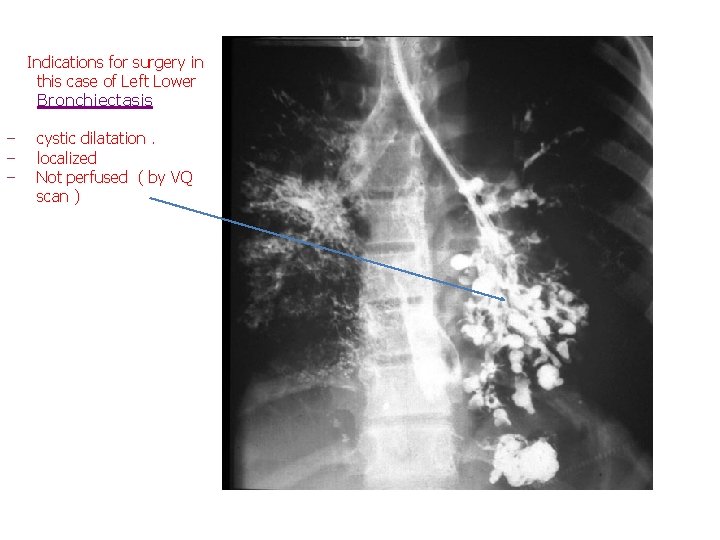

Investigation § Bronchogram ( invasive : catheter & contrast ) § CT § Bronchoscopy Treatment § Medical ‒ Resolve most cases ( perfused , bilateral , cylindrical ) § Surgical (Indications) ‒ ‒ Failure of medical Rx cystic dilatation not cylinderical Patient with localized disease ( )ﻗﺴﻢ ﻭﺍﺣﺪ ﻣﻦ ﺍﻟﺮﺋﺔ , Not perfused ( doesn’t have arteries for perfusion. . How to know ? By : VQ scan ) P. S : most of the cystic are not perfused ; )

Indications for surgery in this case of Left Lower Bronchiectasis ‒ ‒ ‒ cystic dilatation. localized Not perfused ( by VQ scan )